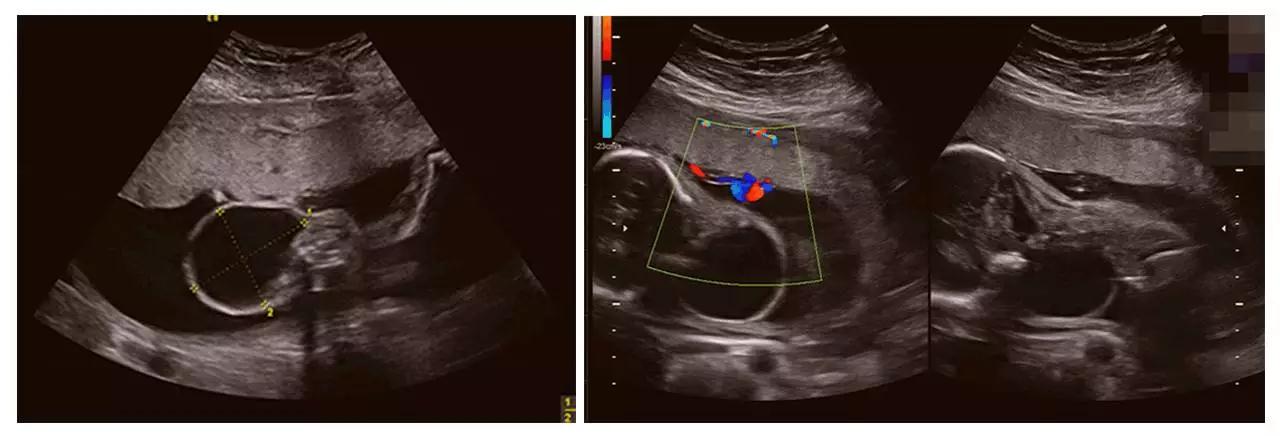

美国GE不仅能提供包括腹部、血管、小器官、产科、妇科、泌尿科、新生儿和儿科等多领域的多方面的应用,而且能够显示未出生的宝宝的实时动态活动图像,为胎儿进行宫内拍“写真”和动态录像,让宝宝拥有最完整的0岁相册。通过四维彩超(四维彩超),可以看到宫内胎儿打哈欠、伸懒腰、吮手指等萌萌的动作,让准爸妈们增添了安心和乐趣,不再仅仅是感觉宝宝的呼吸和运动,可以亲眼目睹宝宝的一举一动和乖巧容颜。还可以打印宫内高清写真,作为送给未来宝宝的珍贵礼物!

四维彩超(四维彩超)

宝宝的0岁照片